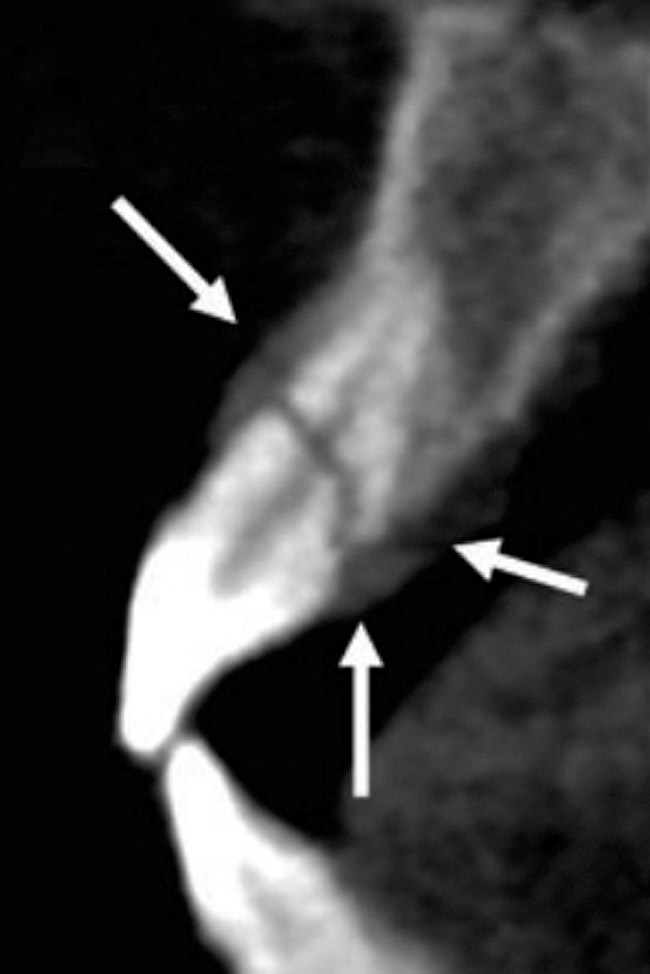

Initially, case studies appeared in the endodontic literature in which patients underwent CBCT imaging for the purposes of diagnosis20-22 and presurgical treatment planning.19 Recent reports have successfully shown the use of CBCT to locate missed canals,23 detect the extent of dentoalveolar fractures,20 identify resorption patterns,22 and compare cystic with granulomatous periapical lesions.17 Figure 2A through Figure 2C show a case in which the missed canal was suggested by periapical radiographs but confirmed with CBCT.24 Similarly in Figure 3A through Figure 3D, the additional diagnostic information attained from CBCT confirmed the diagnosis and extent of the root fracture, which initially was observed in the periapical radiographs (Figure 4A and Figure 4B).20 Notably, the extent of the lingual fracture as well as any alveolar complications could be visualized by CBCT only.

Figure 3a  The 3D capability of the CBCT shows the full extent of the horizontal fracture, as well as the fracture of the buccal and palatal plates.20

Figure 3a

Figure 3b  The 3D capability of the CBCT shows the full extent of the horizontal fracture, as well as the fracture of the buccal and palatal plates.20

Figure 3b

Figure 3c  The 3D capability of the CBCT shows the full extent of the horizontal fracture, as well as the fracture of the buccal and palatal plates.20

Figure 3c

Figure 3d  The 3D capability of the CBCT shows the full extent of the horizontal fracture, as well as the fracture of the buccal and palatal plates.20

Figure 3d